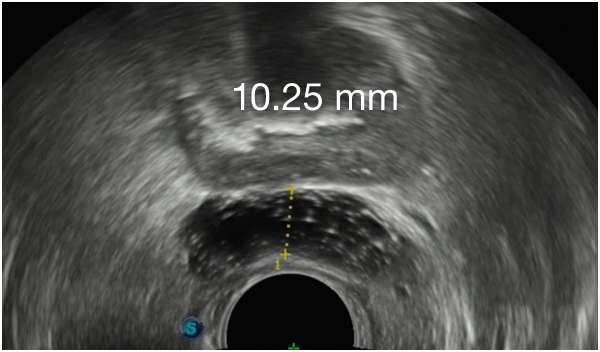

CONSISTENLY CREATE

SYMMETRICAL IMPLANTS,

FROM DAY 1

CONSISTENLY CREATE SYMMETRICAL IMPLANTS, FROM

DAY 1

First Barrigel Cases - Consecutive Patients (Same Day)

TRUS images courtesy of Daniel R. Welchons, MD

Urologist; New York, United States